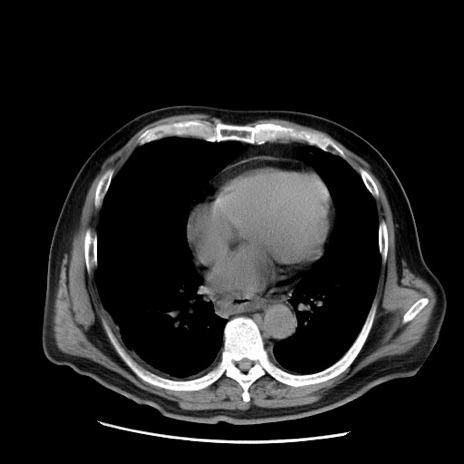

症例20(横断像)

【症例】 60歳代男性

【主訴】 腹部膨満、嘔吐

【現病歴】5日前頃より倦怠感を認め食事量減少し4日前の朝嘔吐、食事摂取困難となった。 3日前近医受診し点滴施行され整腸剤などを処方された。 当日他院を受診し、腹部膨満著明、炎症反応の上昇(CRP10.8、WBC11200)あり、紹介受診となる。

【既往歴】 躁うつ病(抗精神病薬多数内服あり)

【身体所見】 意識JCS1 受け答えがはっきりしないBP 111/57mHg、 P 67bpm、、BT35.2°C、SpO2 97%(RA)、 腹部:膨隆、打診で鼓音あり、全体的に圧痛有り、腸蠕動音(-)、反跳痛ははっきりせず。

【データ】WBC 11400、CRP 14.20